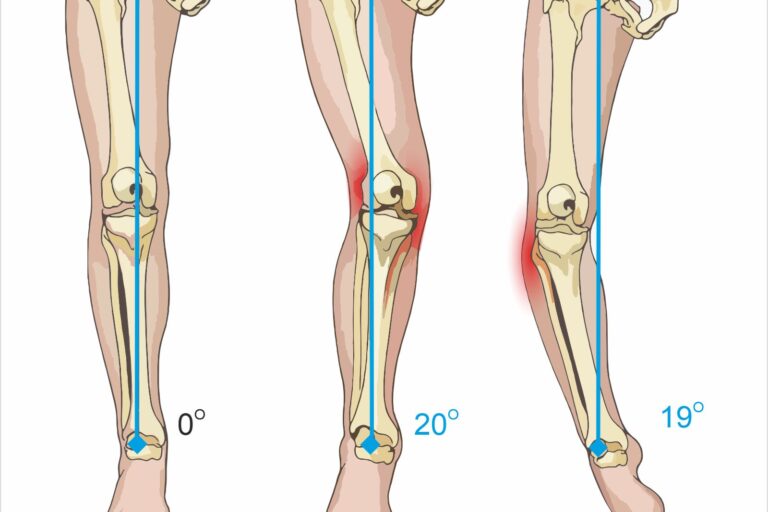

Jako ortopeda często spotykam pacjentów, którzy zaczynają biegać i na samym początku mają dolegliwości bólowe. Bardzo często są to osoby w wieku ok. 30-40 lat, które dotychczas spędzały czas mało lub niezbyt aktywnie.  Po nagłym oderwaniu od biurka, ich układ kostno-mięśniowy nie jest przygotowany do obciążeń treningowych, co skutkuje uszkodzeniami mięśniowo-kostnymi a w konsekwencji kontuzjami. Jest to bardzo deprymujące i zniechęcające. Ja jednak uważam, że nie ma powodów do rezygnacji z biegania! Nikomu nie odbieram prawa zostać maratończykiem! Czeka nas jednak więcej pracy. Być może należy zrobić krok w tył i zacząć od ćwiczeń rozciągających i ogólnorozwojowych, które stopniowo należy łączyć z treningiem biegowym. Należy tylko przygotować organizm do obciążeń biegowych. Bardzo często nasze stawy nie są rozćwiczone, a mięśnie rozciągnięte, podczas biegu nie pracują prawidłowo i podlegają niefizjologicznym obciążeniom, co jest powodem kontuzji.